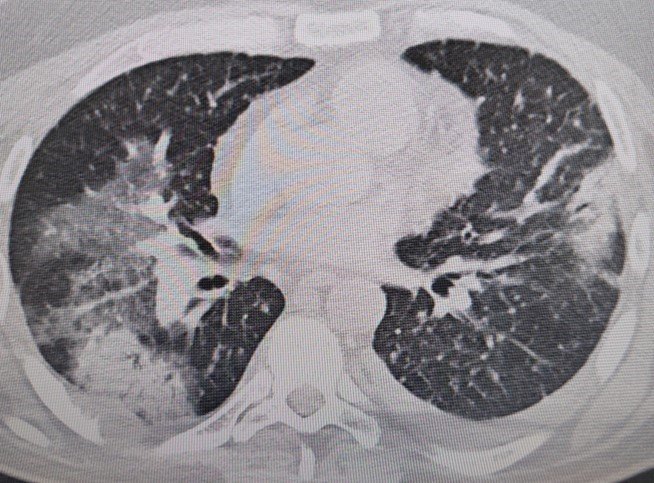

Prof. Dr. Şevket Özkaya, "Legionella" bakterisinin klima sularında üremesiyle insanların yaz zatürresine yakalandıklarını ve kış aylarına göre çok daha fazla vakayla karşılaştıkları bilgisini verdi. Klima zatürresinin özellikle kronik rahatsızlığı olanlarda ölümcül olabileceğini belirten Prof. Dr. Şevket Özkaya önemli uyarılarda bulundu. Özkaya, "Klimaların havalandırılmasıyla beraber insanlar "lejyoner" bakterilerini akciğerlerine aldığında "klima pnömonisi" ya da "yaz zatürresi" dediğimiz hastalığa yakalanıyorlar. Bunun özellikle kronik astım, KOAH ve kanser hastalarında ölümcül sonuçlar doğurabileceğini biliyoruz" dedi.

Özellikle klimaların iyi temizlenmesi gerektiğini ifade eden Prof. Dr. Özkaya, "Klima zatürresinde grip gibi belirgin değil. Eklem ağrıları, ateş, halsizlik, ishal gibi hafif soğuk algınlığı belirtileriyle seyrettiği için de hemen anlaşılmayabilir. Özellikle kronik hastalığı olanlarda hayati sonuçlar doğurabilir. Ani ısı değişiklerine, örneğin sıcaktan soğuya ve klimalara maruz kalmakla oluşan belirtiler korona ile de karışabilir. Vatandaşlarımız, özellikle kapalı yerlerde kendilerine dikkat etsinler. Klima ayarlarını 22 derecenin altına düşürmesinler. Özellikle de bu ısı değişimlerine uzun süre maruz kalmamalarını öneriyorum" şeklinde konuştu.